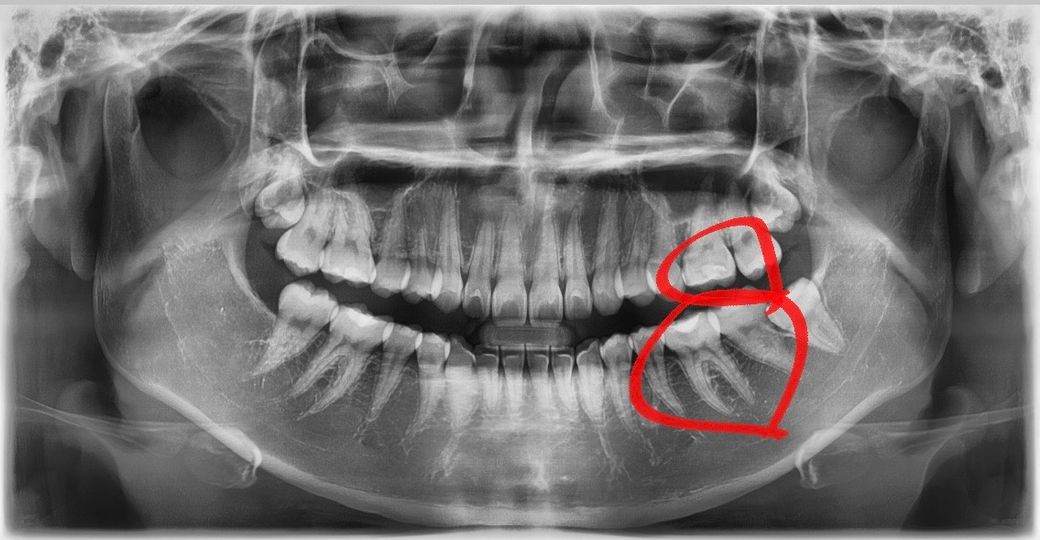

치아 왼쪽 위는 레진으로 저번에 깊게 때웠는데

들떠서 다시 해야 하고

왼쪽 아래는 레진으로 때운 곳 밑에 까맣게 보이는

부분이 충치 같다고 하셔서요!

둘 다 인레이로 해야 할 것 같다고 하셨는데

다른 전문가 분들이 보시기에도 그럴까요?

• 1번 째 사진